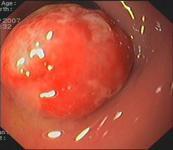

結腸息肉癥狀

• 結腸息肉

628健康網為您分享有關結腸息肉的癥狀,結腸息肉的治療方法,結腸息肉的預防知識,結腸息肉的癥狀圖片,結腸息肉吃什么藥,結...